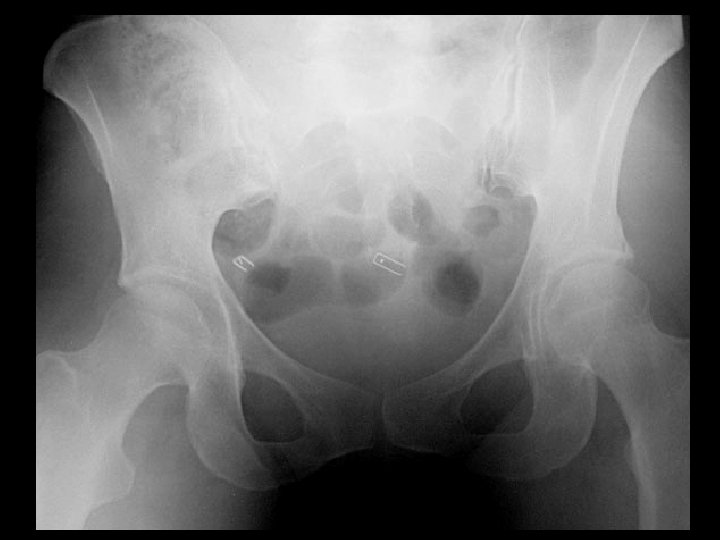

Hyperparathyroidism & Dystrophic soft tissue Ca+ • Findings: – Abnormal soft tissue Ca 2+ in the anterior pelvis – Vascular Ca 2+ • ddx: – Tumoral calcification – Myositis ossificans progressiva

Paget’s disease • Findings: – trabecular and cortical thickening involving the left hemipelvis and proximal femur • ddx: – slcerotic mets (unlikely)